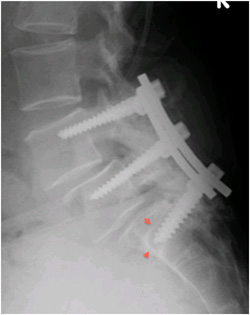

Bel kayması ameliyatında amaç, kayan iki omuru hareketsiz hale getirerek iki omurun birbirine kaynamasını (füzyon) sağlamaktır. Bu kaynama, operasyondan sonra aylar içerisinde tamamlanmaktadır. Kaynamanın daha çabuk ve güçlü olması için kaymış olan hareketli omurları birbirine sabitlemek (fiksasyon) gerekir. Bunun için vida-rod, sistemi gibi birtakım farklı sistemler kullanılır (Spinal Enstrümantasyon). Bel kayması tedavisinde uygulanan bu operasyonun genel adı Spinal Enstrümantasyon ve Füzyon dur. Ancak çeşitleri vardır. Bunlar arasında en güçlü ve en hızlı füzyon sağlayan teknik, Transpediküler Fiksasyon ve İnterbody Füzyon dur. Bu amaçla titanyum vida, plak ve rodlar kullanıyoruz. Bunlar MR ile uyumludur. Daha sonra hastalara herhangi bir nedenle MR çekilmesine engel teşkil etmez. Açık olarak yapılan bel kayması ameliyatları son yıllarda kapalı olarak uygulanmaya başladık.